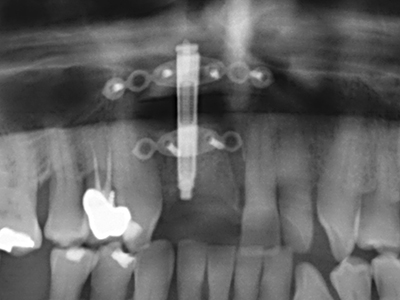

Индикация: Апикална резекция

Както е отбелязано по-горе, индикациите за пиезохирургия могат да бъдат открити и в сферата на консервативната дентална хирургия. Специалните работни накрайници улесняват разкритието на кореновите канали и предпазват нервите и мукозната мембрана на синуса, особено в долния премолар и горната дистална зона на зъбите. Извитите диамантени накрайници се използват за прецизна подготовка за резекция на кавитета за ретроградно запълване на канали на незакрита апикална обтурация. Ултразвуковата технология позволява накрайниците да бъдат много тънки, като това подобрява видимостта и размера на достъпа до кавитета. В резултат, приложението на ултразвукова хирургия за тази индикация е една от стандартните процедури за апикална резекция (Del Fabbro, Tsesis et al. 2010, Scarano, Artese et al. 2012).